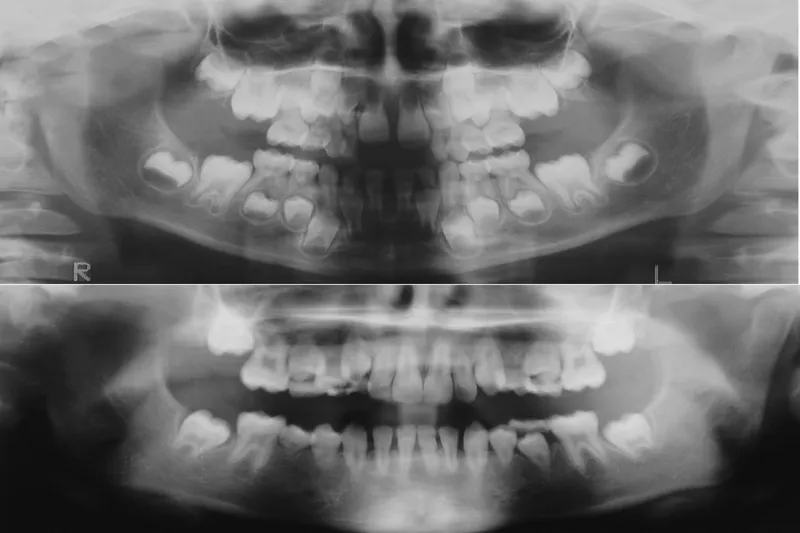

Årligt diagnosticeres omtrent 200 børn (< 18 år) med en cancersygdom. Akut lymfatisk leukæmi (ALL) og hjernetumorer udgør de hyppigste cancerformer hos børn med over halvdelen af tilfældene. Cancer i øvrige organsystemer er sjældnere forekommende. Grundet store fremskridt inden for cancerbehandling de senere år overlever op mod 90 % af de børn, som diagnosticeres med cancer, i dag. Cancerbehandlingen kan imidlertid påvirke barnets vækst, udvikling og organfunktioner, og ofte påvirkes tændernes mineralisering, hvilket kan resultere i varierende grader af tanddannelsesforstyrrelser og afbrudt tanddannelse. I denne artikel gennemgås de almindeligste cancerformer, deres typiske behandlingsforløb og varighed og de typiske tandforandringer, som kan ses efter cancerbehandling i barndommen. Artiklen omhandler desuden sundhedsloven og henvisningspraksis med relevans for området samt aktuelle anbefalinger for så vidt angår forebyggende tandbehandling hos børn og unge med cancer.

Årligt diagnosticeres omtrent 200 børn med en cancersygdom. Prognoserne er overordnet gode, og den samlede forventede overlevelse er på godt over 80 %. Cancerbehandlingen kan imidlertid påvirke barnets vækst og udvikling, og en del (omkring 50 %) har senfølger som konsekvens af cancerbehandlingen. Tandlæger vil derfor møde patienter med senfølger i børne- og ungdomstandplejen og senere, når de kommer i privat praksis som voksne. Cancerbehandlingen kan medføre varierende grader af mineraliserings- og tanddannelsesforstyrrelser, hvilket i nogle tilfælde kan føre til øget risiko for tidligt tandtab, omfattende behandlingsbehov og hvis ubehandlet til væsentlig funktionsnedsættelse. Det er vigtigt at kende til de forskellige typer af afvigelser for at kunne iværksætte optimal forebyggelse og relevant tandbehandling og vurdere, om henvisning til specialiseret oral rehabiliterende behandling er nødvendigt.